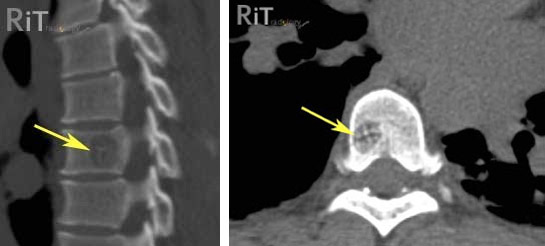

Позвоночные гемангиомы диагностируются с помощью МРТ (магнитно-резонансной томографии) и/или КТ (компьютерной томографии). МРТ-скан использует магниты, радиоволны и компьютерные технологии для создания снимков органов и тканей, таких как головной и спинной мозг. КТ-скан использует комбинацию рентгена и компьютерной технологии для получения детального изображения костей и мягких тканей.

И тот, и другой диагностический метод может проводиться с использованием контрастного вещества, которое «подсвечивает» ткани опухоли. Контрастное вещество также может помочь дифференцировать гемангиому от других опухолей позвоночника.

Сканы позвоночных гемангиом обычно демонстрируют детали, характерные для этих опухолей. Одной из этих деталей является наличие «рубчиков» — вертикальных утолщений в затронутой кости. Эти утолщения чередуются с нормальной костью, складываясь в рисунок, напоминающий рубчики на вельвете. Осевые сканы или сканы, которые показывают горизонтальное поперечное сечение кости, демонстрируют другой признак — «узор в горошек». На этом срезе видны круглые поперечные «шайбочки» утолщенных тканей внутри нормальной кости, напоминающие узор в горошек.